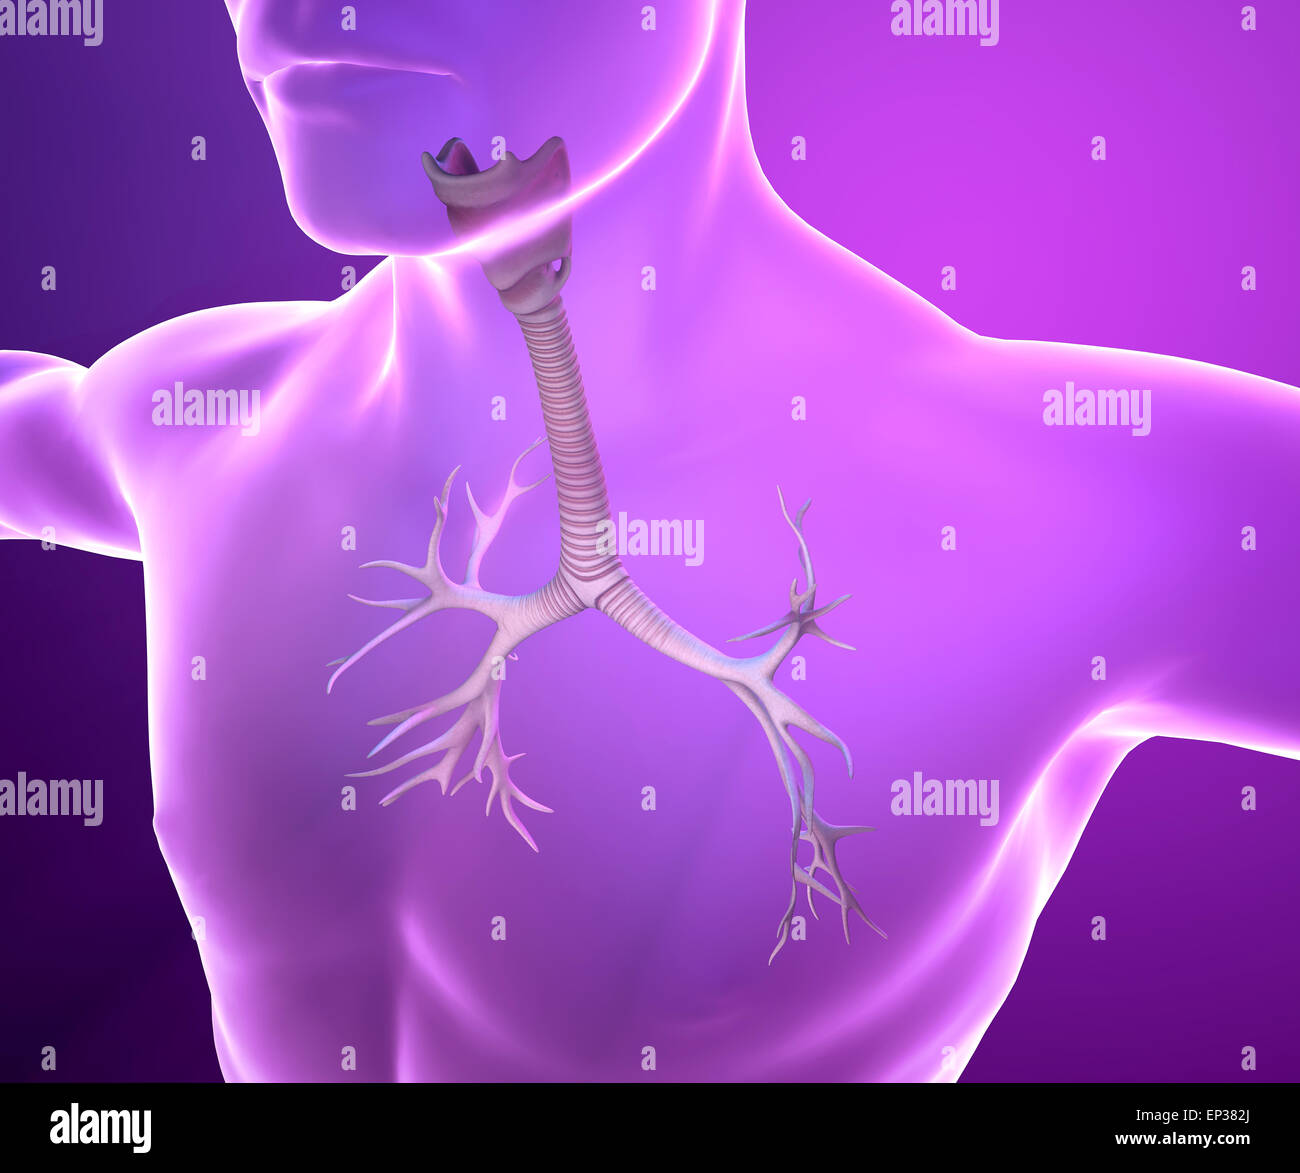

RF2N9P3NT–Röntgen des Schilddrüsenknorpels 3D-Darstellung mit männlichen Körperkonturen. Menschliche Anatomie, Medizin, Biologie, Wissenschaft, Gesundheitskonzepte.